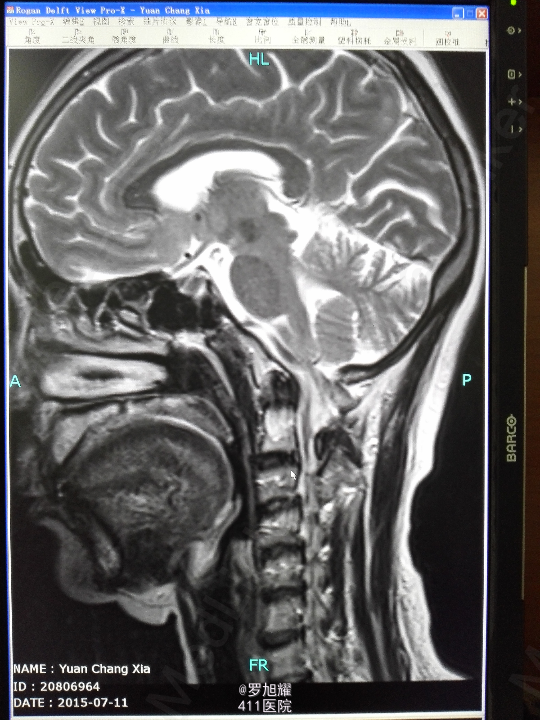

右侧躯体麻木1年,右上肢及下肢麻木2月余。 查体:颈椎活动受限,右上肢肘关节以远痛温觉减退,右侧胸4平面以下痛温觉及触觉减退,四肢肌力尚可,右侧霍夫曼征阳性,右侧上下肢所有腱反射亢进。 颈椎X线示:颈2椎板棘突缺如,颈3棘突肥大增高。 颈椎CT示:颈2椎板棘突缺如,颈3棘突肥大增高,颈2/3椎间盘突出,左侧颈2残留部分椎板进入椎管。枢椎齿突增生,寰枢关节退变。 颈椎MRI示:颈2/3椎间盘突出,左侧颈2椎板进入椎管,颈髓受压变性。

查体:颈椎活动受限,右上肢肘关节以远痛温觉减退,右侧胸4平面以下痛温觉及触觉减退,四肢肌力尚可,右侧霍夫曼征阳性,右侧上下肢所有腱反射亢进。 颈椎X线示:颈2椎板棘突缺如,颈3棘突肥大增高。 颈椎CT示:颈2椎板棘突缺如,颈3棘突肥大增高,颈2/3椎间盘突出,左侧颈2残留部分椎板进入椎管。枢椎齿突增生,寰枢关节退变。 颈椎MRI示:颈2/3椎间盘突出,左侧颈2椎板进入椎管,颈髓受压变性。

诊断为:颈椎先天畸形、颈2/3椎间盘突出伴不全瘫。 因寰枢关节退变,颈椎活动已部分受限,而且枢椎椎板棘突缺如,稳定性差,决定后路减压枕颈融合。

因寰枢关节退变,颈椎活动已部分受限,而且枢椎椎板棘突缺如,稳定性差,枕颈融合虽然造成颈部活动受限,但是稳定性好,避免脊髓再次损伤。本例手术后半月上肢麻木明显改善,躯干和下肢麻木尚待恢复。